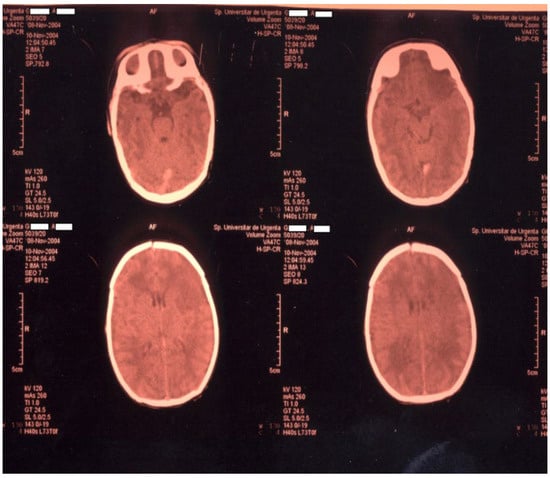

Newborn #1 (3000 g/50 cm, female) was born at 36–37 weeks of gestation by caesarean section after an uneventful pregnancy and was the first child of a healthy mother. The Apgar score was 9, the transition to the extrauterine environment was smooth, and the clinical examination after birth was normal. At 36 h of life, the baby developed tonic–clonic seizures of the left hemibody associated with cyanosis, apnea, and bradycardia and was admitted to the NICU. The baby was tested for metabolic causes of the seizures; a lumbar puncture and inflammatory panel and bacteriologic tests were performed, and phenobarbital was started. Because of recurrent apneic spells, respiratory support was initiated, and imagistic investigations were ordered. Head ultrasonography raised suspicion of a large right frontal–parietal infarction, confirmed later through Computer Tomography (CT) and Magnetic Resonance Imaging (MRI)—see Figure 1 and Figure 2. Echocardiography revealed no abnormalities. Laboratory tests were all within normal limits, except a mild thrombocytopenia (105,000/mmc).

Figure 1. CT examination for newborn #1.